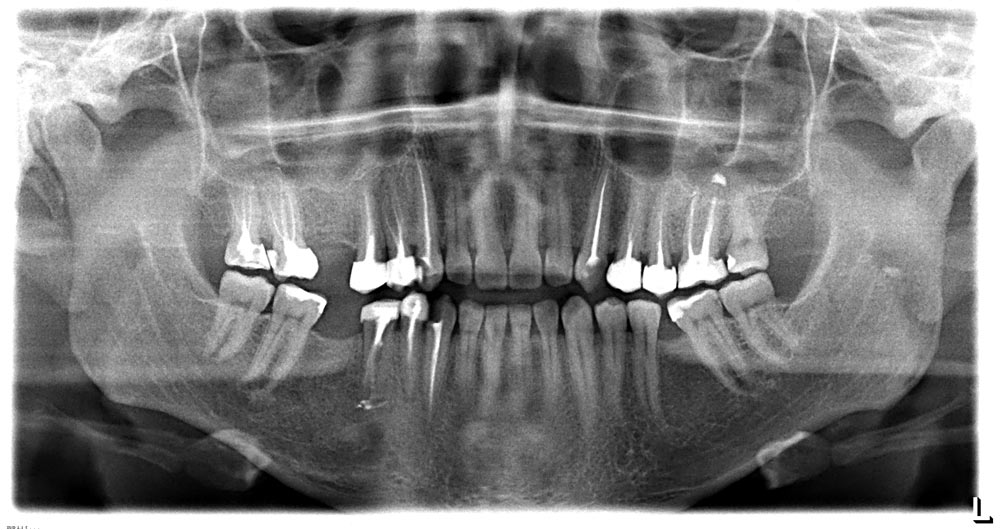

მიმაგრებული სურათი (გადიდებისთვის დაუწკაპუნეთ სურათზე)